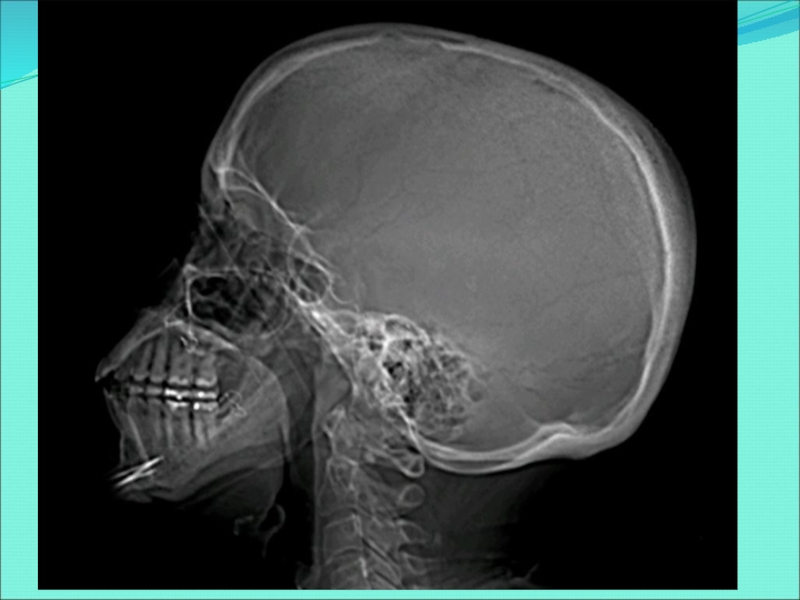

Слайд 27ЧЕРЕП НОВОРОЖДЕННОГО

Мозговой отдел черепа по объему в 8 раз больше

лицевого отдела (в результате активного роста мозга и раннего формирования

органов чувств).

Основание черепа по сравнению со сводом отстает в росте, кости соединены друг с другом посредством широких хрящевых и соединительнотканных прослоек.

Лобная кость состоит из двух половин, надбровные дуги отсутствуют, лобной пазухи еще нет.

Челюсти недоразвиты, что обусловливает малую высоту лицевого отдела черепа.

Нижняя челюсть состоит из двух частей (двух половин).

Слайд 28ЧЕРЕП НОВОРОЖДЕННОГО

6. Бугры лобной и теменных костей хорошо выражены (при

рассматривании черепа сверху он кажется четырехугольным).

7. Части височной кости

отделены друг от друга хорошо выраженными щелями, содержащими соединительнотканные или хрящевые прослойки, сосцевидный отросток не развит.

8. На костях черепа не выражены мышечные бугры и линии.

9. Швы между костями свода черепа не сформированы, края костей ровные.

Слайд 29РОДНИЧКИ ЧЕРЕП НОВОРОЖДЕННОГО

Передний (лобный) родничок, зарастает на 2-м году жизни.

Задний (затылочный) родничок, зарастает на 2-м месяце жизни.

Клиновидный родничок,

зарастает на 2-3-м месяце жизни.

Сосцевидный родничок, зарастает на 2-3-м месяце жизни.